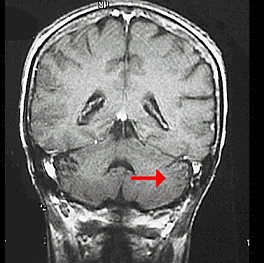

如图箭头所示为大脑哪个部位()<img border="0" style="width: 299px; height: 224px;" src="

[单选题]如图箭头所示为大脑哪个部位()A.前连合B.后连合C.室间孔D.穹窿E.中脑导水管